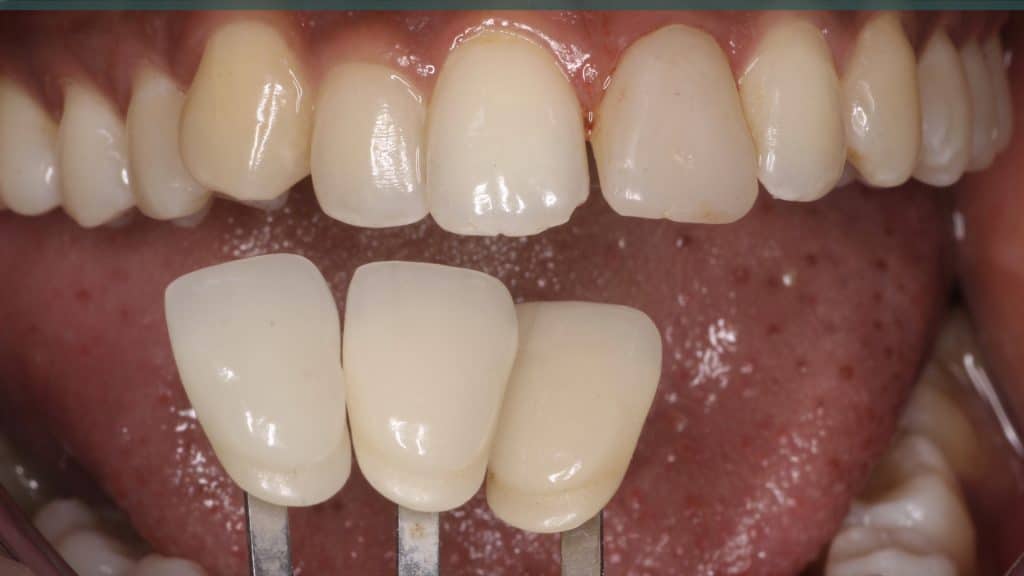

A 27-year female patient with dislodged Resin bonded FPD. She had that FPD for past few years, it had metal wings on palatal surfaces of UR1 and UL2 and a post like metal extension into the root canal of UL1. There was gingival abscess due to fractured root segment most probably due to extended metallic post like structure. Immediate implant placement (IIP) and Immediate restoration (IR) was planned for this patient.

20 days post-op after suture removal